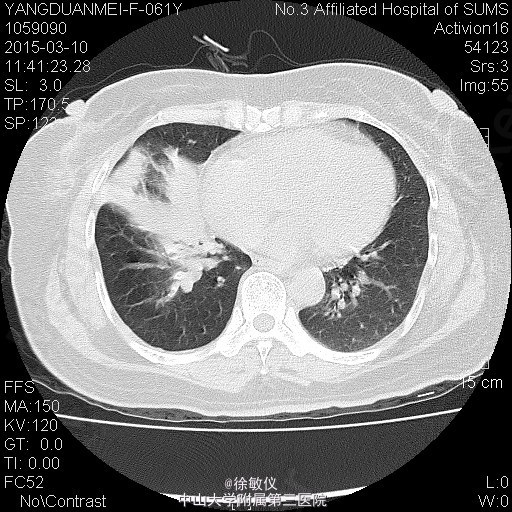

老年女性,主诉:咳嗽2月,胸部CT发现中央型肺癌1天。 现病史:患者2月前无明显诱因出现咳嗽伴胸闷气促,伴少量白色粘液痰,无痰中带血、咯血等不适,当时自行服用“消炎药”治疗(具体不详),2月来症状逐渐加重,至当地医院就诊,查胸部CT提示:右侧中央型肺癌并纵隔淋巴结转移,肝脏考虑转移灶。现为求进一步治疗入院。近期体重减轻2斤。 查体:生命体征平稳,全身浅表淋巴结未扪及肿大。心肺腹查体无特殊。 胸部CT:1、右下中央型肺癌,并右肺门及纵隔多发淋巴结转移;右中间段支气管、中下叶支气管狭窄、闭塞,右肺阻塞性炎症,考虑右侧肺动脉、右下肺静脉受侵。2、肝S4、S8转移瘤。 诊断: 右侧中央型肺癌并肝转移。